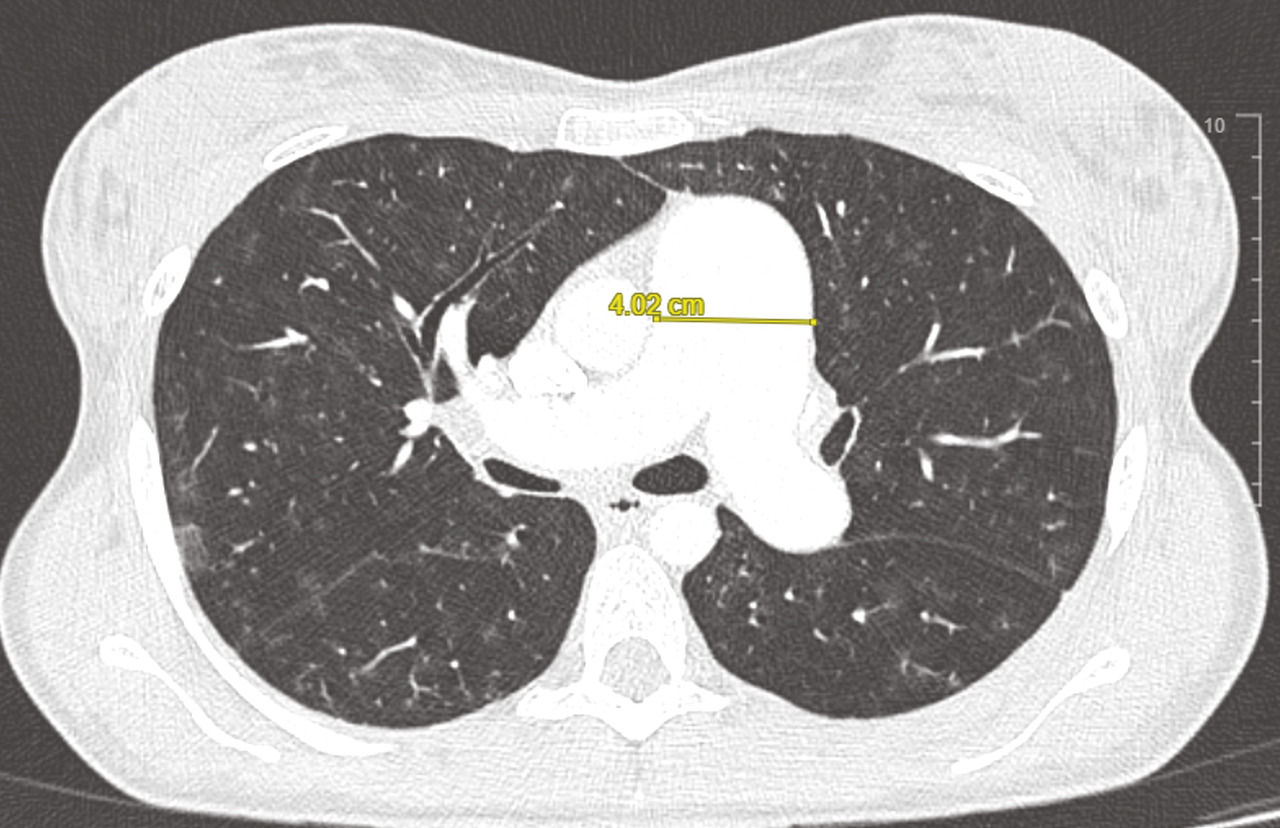

Le scanner thoracique en coupes millimétriques permet de rechercher des éléments évocateurs de maladie veino-occlusive pulmonaire (épaississement des septa, nodules flous en verre dépoli, adénopathies médiastinales) ou d’une pathologie respiratoire sous-jacente (emphysème, pneumopathie interstitielle diffuse…) [fig. 4 et 5].1,2Un angioscanner thoracique est indispensable pour le bilan d’opérabilité des patients atteints d’HTP-TEC.

L’injection de produit de contraste au temps artériel pulmonaire (angio-TDM thoracique) permet de rechercher des lésions thromboemboliques chroniques.